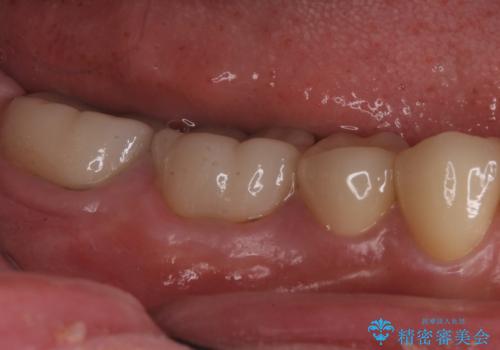

樹脂で継ぎ接ぎになった歯 セラミッククラウンでの治療

- 樹脂の材料の着色が気になるとのことで来院されました。

継ぎ接ぎになっている部分が多かったためクラウンでの治療となりました。

- 右下45:仮歯+ジルコニアクラウン/11,000円+110,000円費用は治療当時の料金となります

樹脂の材料と歯の境界部分は虫歯・着色の好発部位となります。

度重なる治療で継ぎ接ぎになってしまった場合はクラウンで歯を覆った方が虫歯・着色のリスクを減らすことができます。